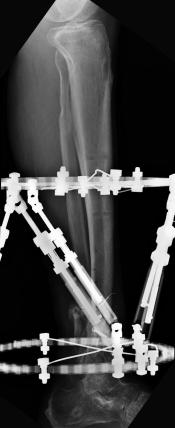

Postoperative (14th) images of left ankle

The image(s) displayed here were created following Liam's 14th surgery which was performed by Dr. Saunders. It was thought that the bones

in the ankle had fused, but during surgery it was discovered that the ankle was a total non-union. The halo frame was removed and 3 anchors were

placed on the tibia. Also added to the ankle was all available Medtronic Infuse material (rhBMP). One image may provide proof that Dr. Saunders

is possessed. ;-) The first set of x-ray shots were taken 3 weeks after the 14th surgery. The 3 new claw anchors are visible as seen through

the cast. Excess bone debris was also removed. Some of the photos had to be taking with the cell phone since the main camera failed. The last

x-rays show that some of the screws in the claw anchors are backing their way out of the leg. The next phone photos show that a screw from a

claw anchor was actually sticking out of the leg and could easily be removed (by hand) by the doctor. The very last photo is of the leg wrapped

in a black cast. Black was used to signify the loss that was soon going to occur. :-(